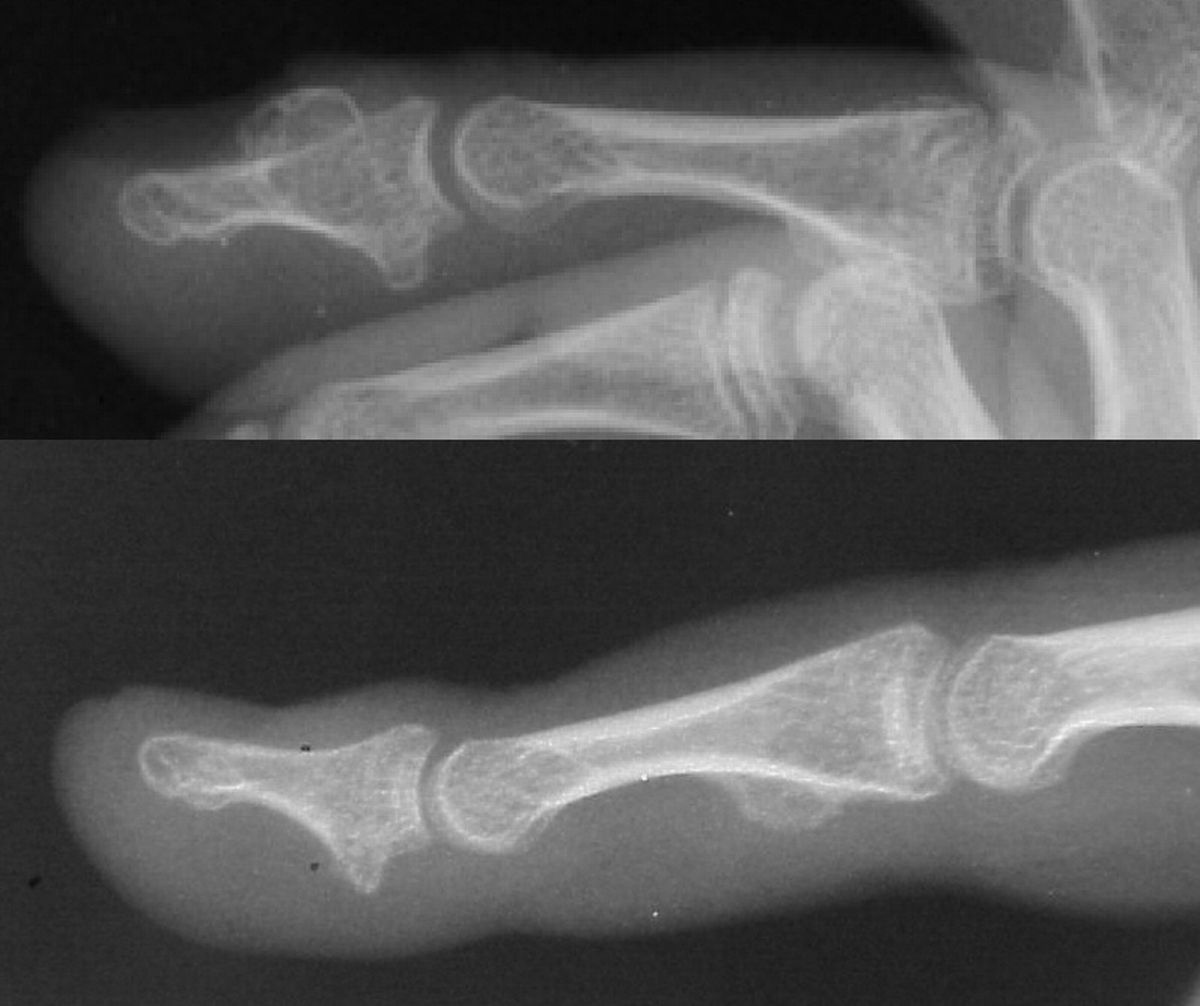

Nail deformity from subungual bone tumor. This patient has multiple hereditary exostoses.

Highslide